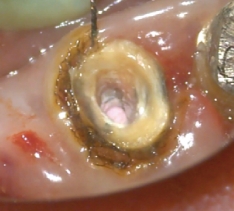

HFC(High Frequency Conduction:高周波通電)

高周波通電により、チップ電極の先端部と接触した部位を発熱させることで、組織の焼灼・凝固・切開を行うことができます。

根管長測定機能によって根管内のチップ電極の位置を設定し、フットスイッチを踏むことで1秒間のHFCが行えます。

2タイプのチップ電極を付属。どちらでも根管長測定、HFCが行えます。

チップ電極(ファイルタイプ) -

チップ電極(エンドファイルタイプ)

マイクロスコープ利用時の術野確保に有効です。